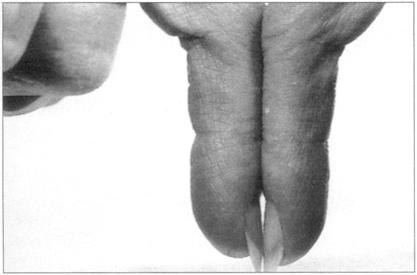

同心血管系统检查相似,呼吸系统习惯上也从检查双手开始,病人以45°头高位躺在床上。寻找杵状指,即指甲在两个方向上弯曲度增加,失去了正常的指甲角。这是由于甲床和指尖的软组织增生引起。有时指甲变化很小不易发现,在这种情况下,可以寻找钻石征(菱形征)(见图64),正常人双手指甲相对,两指甲根部之间可观察到一个小的菱形裂隙。杵状指由于指甲角丧失无法看到该裂隙。杵状指的病因很多,这里不重复了,但记得较常见于支气管癌、慢性脓胸、纤维性肺泡炎。我们也要寻找二氧化碳潴留的体征——跳跃性脉和外周静脉扩张引起的双手变暖。让患者伸出双手寻找扑动性震颤——即双手不规则的抽搐运动。二氧化碳高于正常水平会引起外周发绀。

图64 菱形征:在正常的个体当中,在指甲反折处可见菱形,如果患者的手指是棒状的,这种表现将更明显